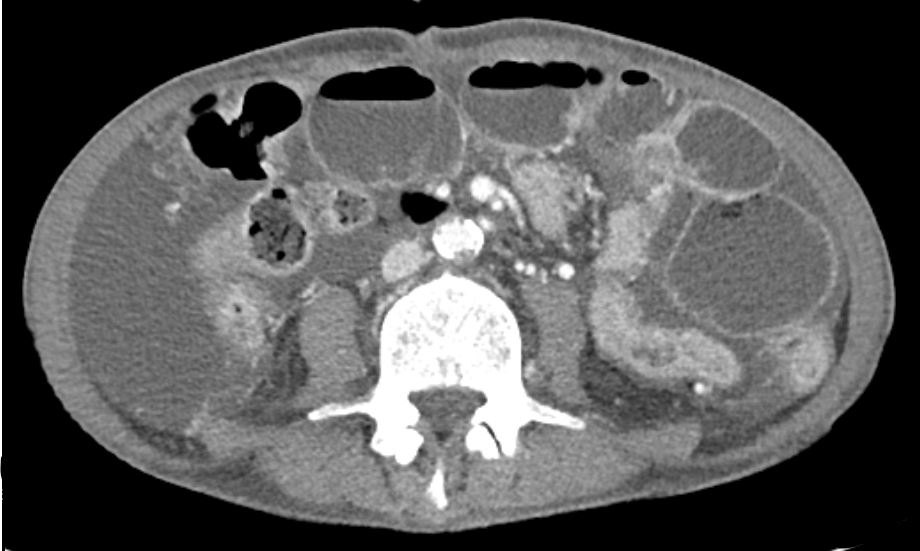

CT: Multiple air-fluid levels in small intestine, small intestinal dilatation and wall thickening, ascites

• AXR상 step-ladder sign이 확인되므로 소장 폐쇄의 가능성이 매우 높고, CT상에서도 small bowel dilatation과 서로 다른 air-fluid level이 확인된다. 따라서 소장 폐색으로 진단한다.

• 현재 복수도 있는 점으로 보아 pancreatic cancer의 복막 전이가 있으며, 이로 인해 adhesion 또는 tumor에 의한 small bowel compression, obstruction 등이 발생해 장폐색이 발생한 것으로 추정된다.